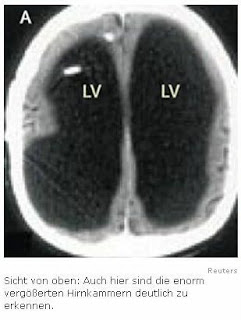

Eine Computertomografie und eine Kernspintomografie bei dem 44-Jährigen hätten «äußerst ungewöhnliche» Bilder erbracht. Das Gehirn des Mannes sei eigentlich nicht wirklich vorhanden. Dies sagte der Arzt Lionel Feuillet vom Marseiller Spital La Timone zu einem Bericht in der jüngsten Ausgabe der Fachzeitschrift «Lancet».

Gemäß neuropsychologischen Untersuchungen habe der Mann einen Intelligenzquotienten (IQ) von ca. 75. Der Durchschnitt liegt heute bei ca. 100. Bei den Untersuchungen habe sich gezeigt, dass die üblichen Hohlräume im Gehirn sich bei dem Mann massiv ausgedehnt hätten, sagte Feuillet. Trotz allem ist er nahezu normal entwickelt und hat sich ein soziales Netz aufgebaut.

«Das Gehirn selbst, also die graue und weiße Nervenmasse, war völlig -wie eine Schale- an den Rand des Schädels gedrückt.» Der zweifache Vater habe trotzdem ein normales Leben geführt.

Erkennbar sind die mit Flüssigkeit gefüllten Ventrikel (schwarze Fläche, Bild oben). Normalerweise weist die Gehirnrinde eine Dicke von etwa 4 Zentimetern auf, bei ihm war sie jedoch auf die Dicke eines Papierblattes zusammengeschrumpft. Dr. Lorber schätzte, dass das gesamte Gehirn des Mannes nur etwa 100 Gramm wog. Ein normales Gehirn eines Erwachsenen wiegt zum Vergleich etwa 1,3 Kilogramm, also 13-mal soviel. Der Student litt unter einem Wasserkopf, einer Krankheit, bei der die Gehirn-Rückenmark-Flüssigkeit anstatt um das Gehirn zu zirkulieren und anschließend in den Blutstrom überzugehen, im Inneren aufgestaut wird.